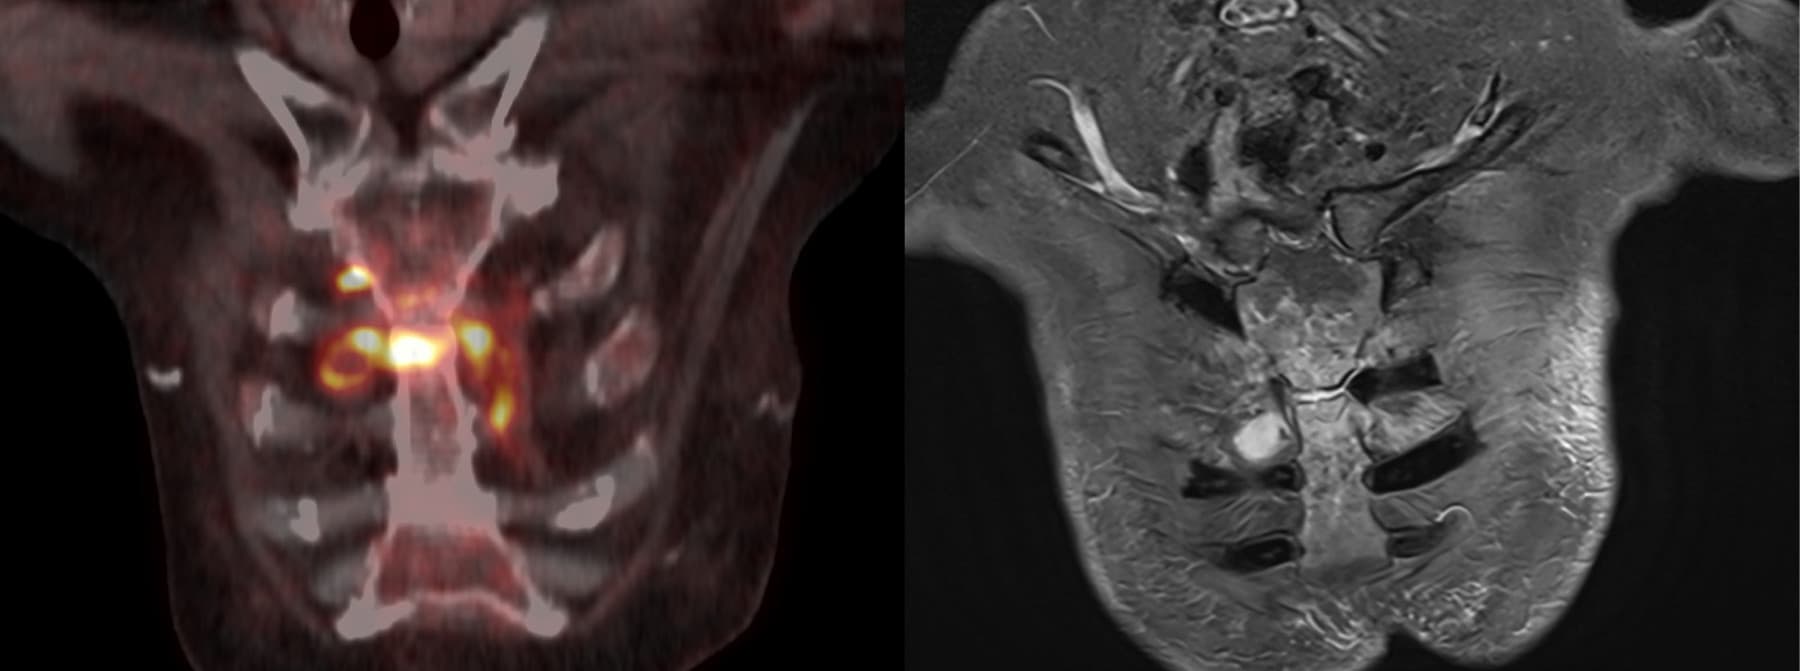

En ældre, multimorbid kvinde, indlagt med Escherichia coli-pyelonefritis og bakteriæmi, responderede initialt på relevant antibiotikabehandling. Pga. stagnerede infektionstal blev der udført FDG-PET/CT på mistanke om sekundært infektionsfokus/malignitet. Ud over pneumoniske infiltrater og pyelonefritis sås overraskende kraftig 18F-fluordeoxyglukose (FDG)-optagelse i manubriosternalleddet og nærliggende bløddele, men kun diskrete CT-forandringer. Klinisk fandtes hævelse over manubrium sterni og ømhed parasternalt. Efterfølgende MR-skanning viste septisk artritis, og parasternalt, interkostalt, højresidigt sås desuden en mindre absces. Gentagne forsøg på aspiration mislykkedes. Trods manglende mikrobiologi var sternal E. coli-infektion efter hæmatogen spredning fra urinvejene den mest sandsynlige diagnose.

Kun få lignende tilfælde kendes, idet de øvrige (også sjældne) tilfælde af E. coli-kostochondritis er primære (kirurgi, traume eller pleural infektion) [1, 2]. Infektionsudredning med FDG-PET anbefales blandt andet ved mistanke om ukendt, sekundært infektionsfokus samt hos risikopatienter med bakteriæmi [3].

Aktuelle case viser værdien af FDG-PET til påvisning af uventede/atypiske infektionsfoci, der kun vanskeligt ses på CT.